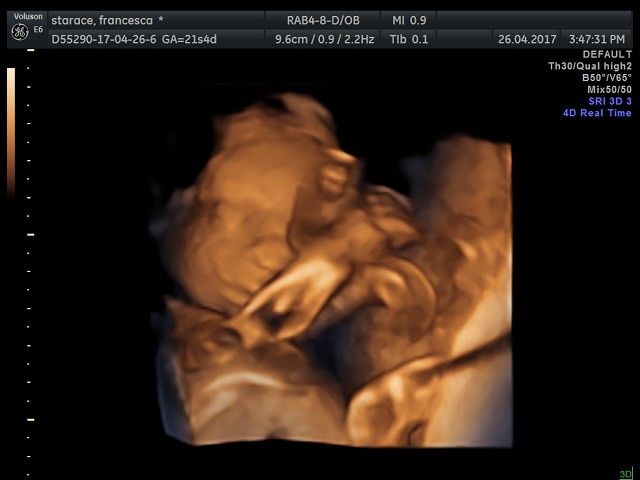

Ciao ragazze, in un attacco di insonnia vi posto le foto della morfologica in 4d di ieri๐Ÿ˜! La polpetta sta alla grande, pesa 430 gr ed รจ tale e quale al papa!๐Ÿ˜‚๐Ÿ˜‚๐Ÿ˜‚tutti questi mesi nella pancia con noi mamme, e poi sono la fotocopia dei mariti!!!๐Ÿ˜‚๐Ÿ˜‚๐Ÿ˜‚un bacio da me e e Bianca 21+5๐Ÿ’–notte!!!!

Morfologica, che spettacolo!!!! - 2